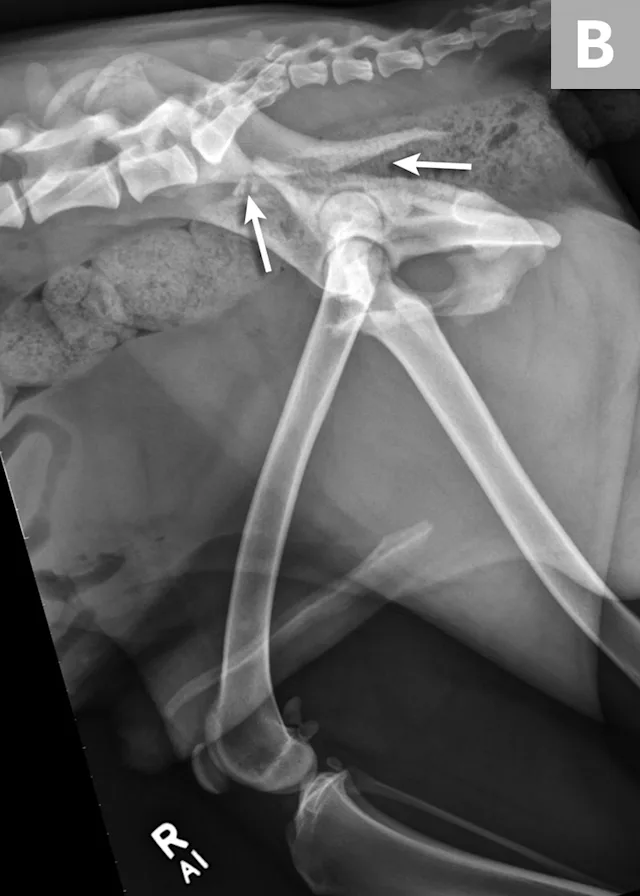

FIGURE 1A

An 11-year-old intact female Welsh corgi with injuries of the weight-bearing axis of the pelvis. Ventrodorsal (A) and lateral (B) projection images show a left sacroiliac luxation with cranial and ventral displacement (black arrow). Pubic fracture with lateral displacement (dashed arrow) and an oblique tibial fracture (white arrows) were additional comorbidities. The tibial fracture was treated surgically with an internal plate fixation, and the pelvic injuries were managed conservatively.